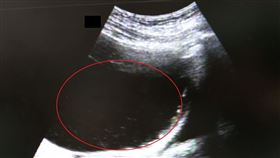

有位罹患慢性B型肝炎、肝硬化合併脾腫大的老翁,經超音...